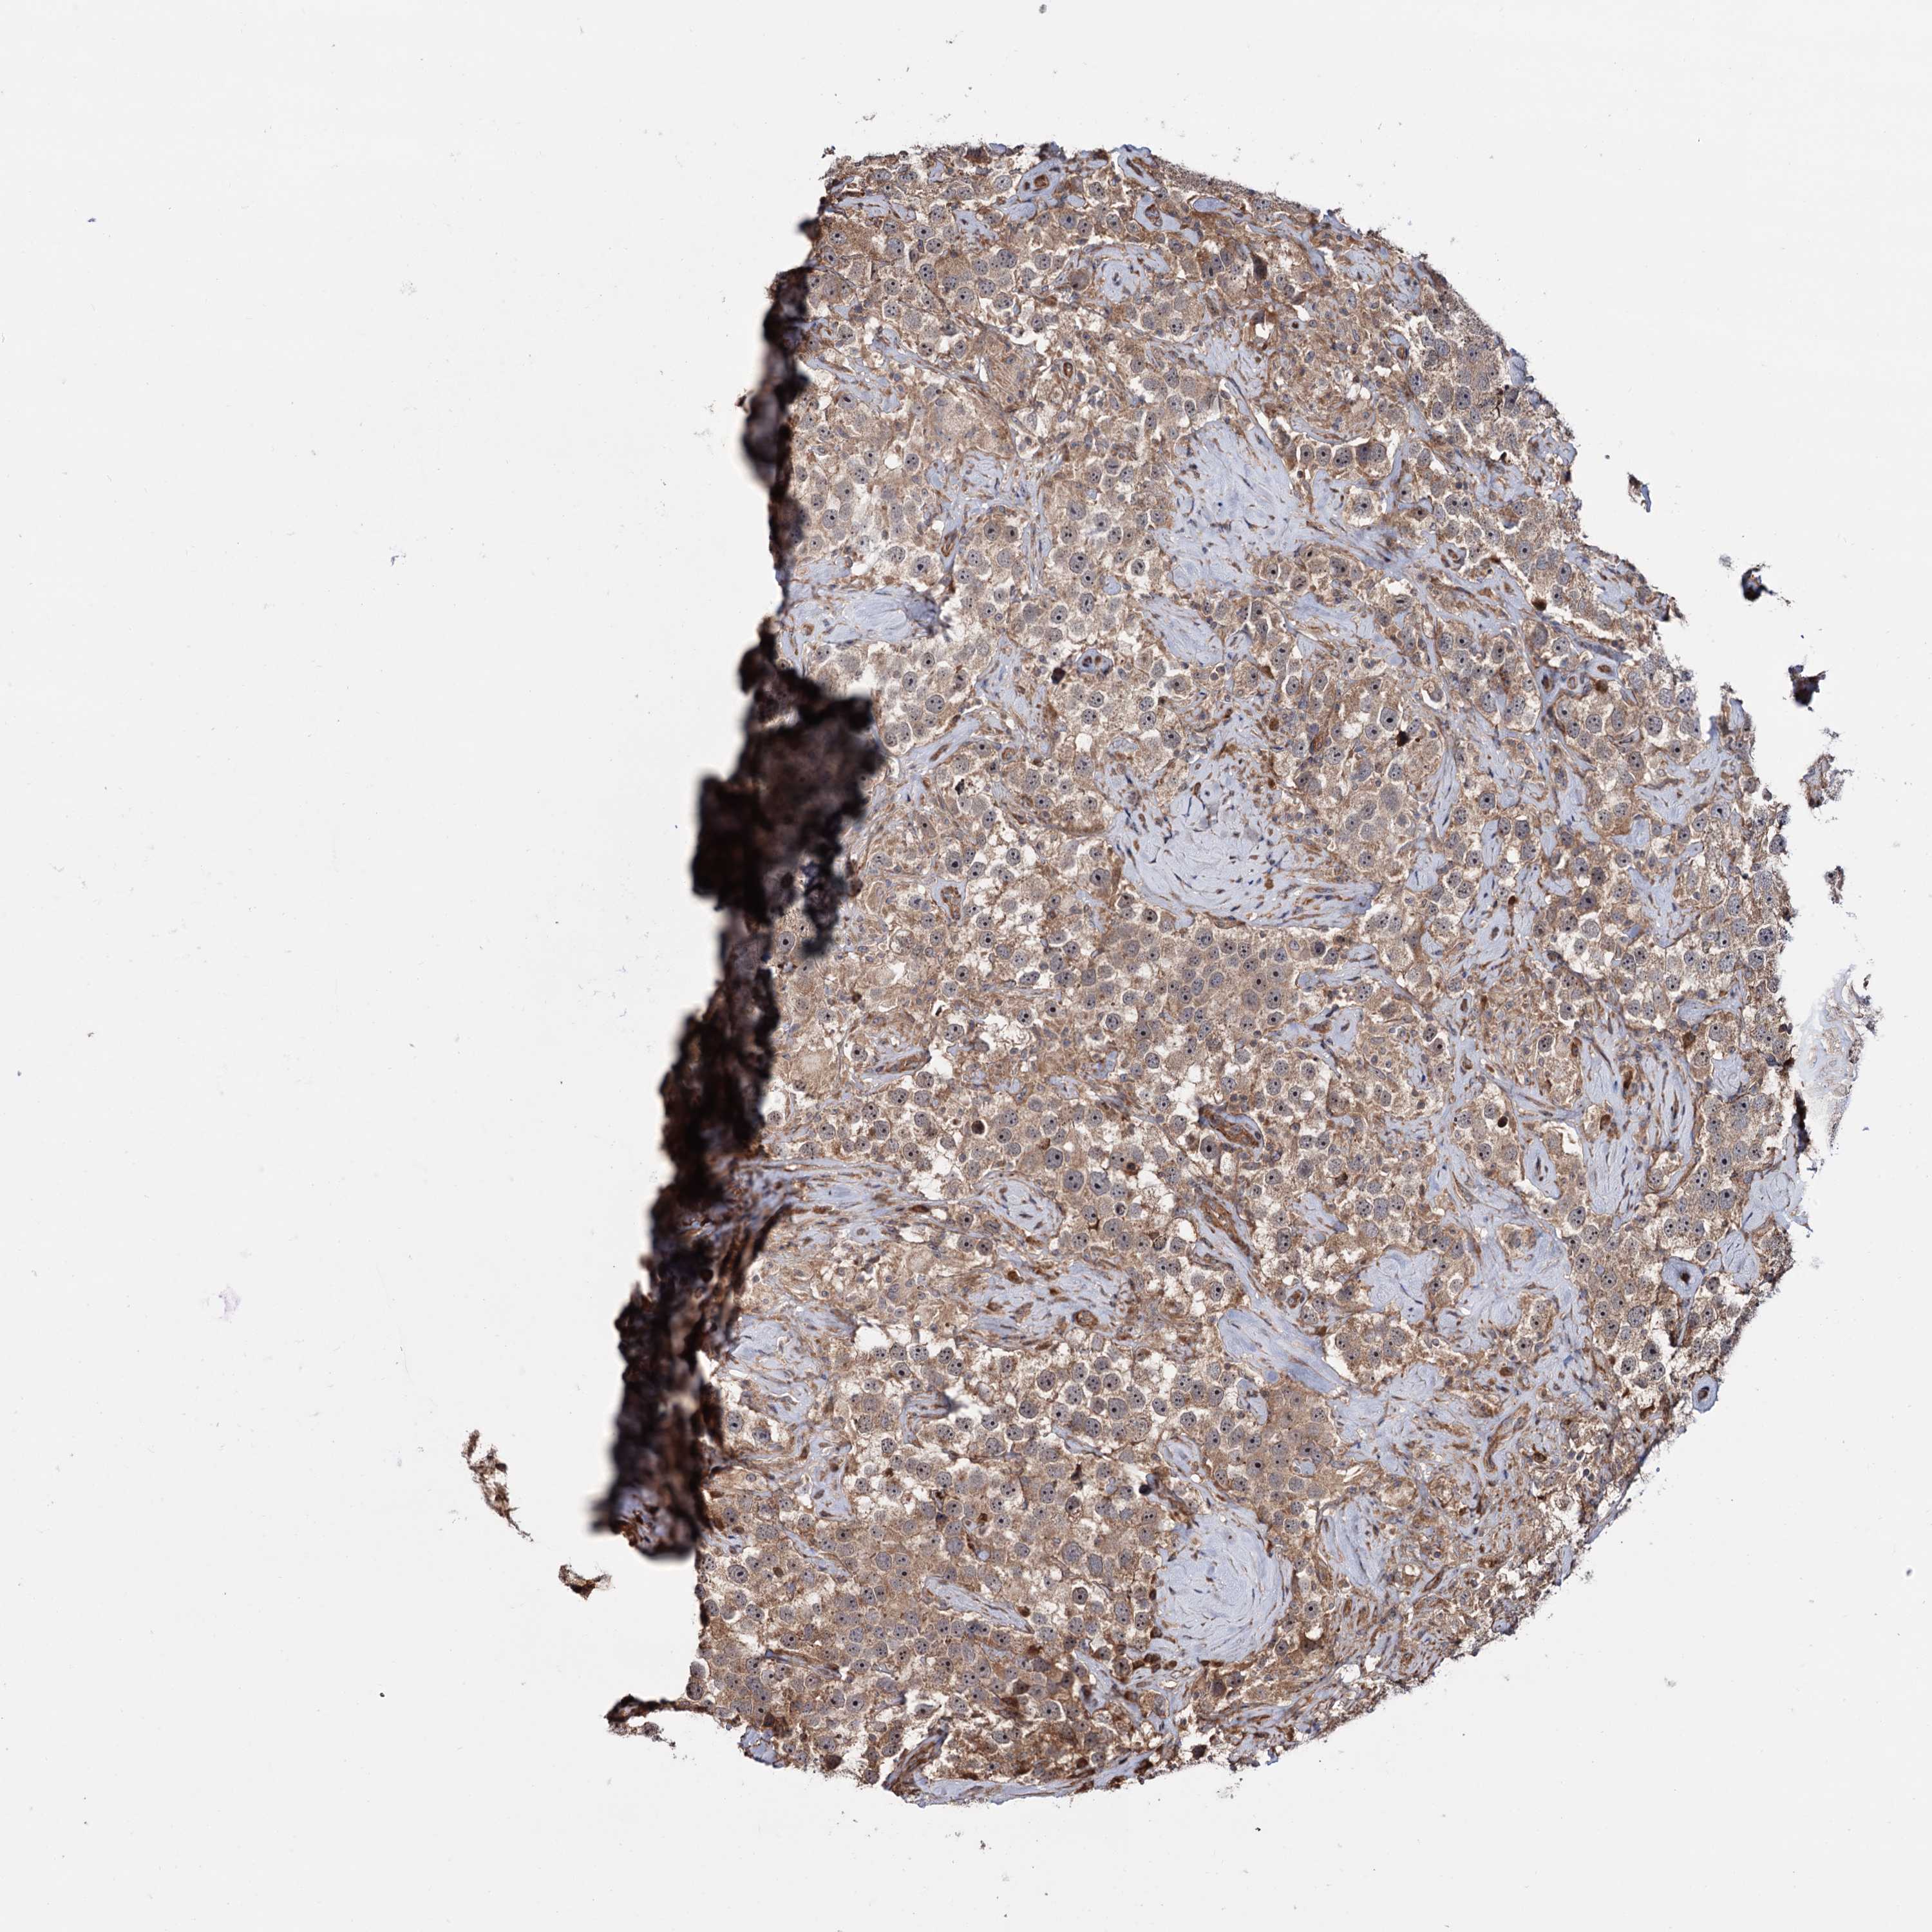

TESTIS CANCER - Protein expressioni

A mouse-over function shows sample information and annotation data. Click on an image to view it in a full screen mode. Samples can be filtered based on level of antibody staining by selecting one or several of the following categories: high, medium, low and not detected. The assay and annotation is described here.

Note that samples used for immunohistochemistry by the Human Protein Atlas do not correspond to samples in the TCGA dataset.

Antibody stainingi

Antibody staining in the annotated cell types in the current human tissue is reported as not detected, low, medium, or high, based on conventional immunohistochemistry profiling in selected tissues. This score is based on the combination of the staining intensity and fraction of stained cells.

Each image is clickable and will lead to virtual microscopy that enables deeper exploration of all samples and also displays staining intensity scores, fraction scores and subcellular localization as well as patient and tissue information for each sample.

Antibody HPA040505

Staining

High

Medium

Low

Not detected

Intensity

Strong

Moderate

Weak

Negative

Quantity

>75%

75%-25%

<25%

None

Location

Nuclear

Cytoplasmic/membranous

Cytoplasmic/membranous,nuclear

Carcinoma, Embryonal, NOS

Seminoma, NOS

Urothelial carcinoma, High grade